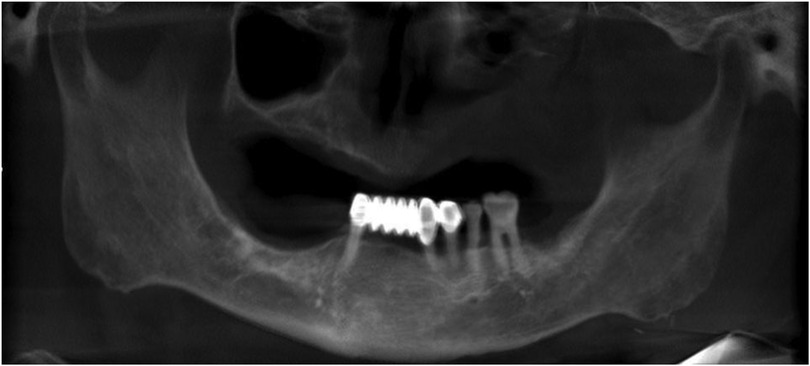

2.3 Imaging studies

(Figure 3).